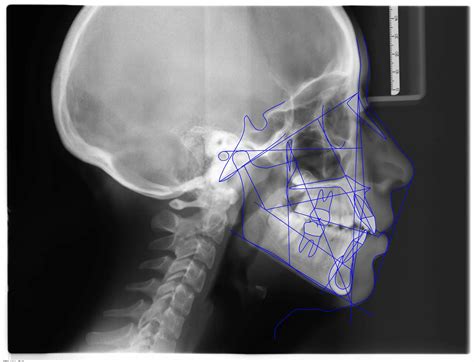

Teleradiografía Lateral de Cráneo

Las teleradiografías laterales de cráneo son esenciales en los estudios de ortodoncia. Permiten medir los ángulos y proporciones de los huesos faciales, proporcionando información crucial sobre la relación entre las estructuras faciales del paciente. Esta técnica es fundamental para planificar tratamientos de ortodoncia precisos y personalizados.